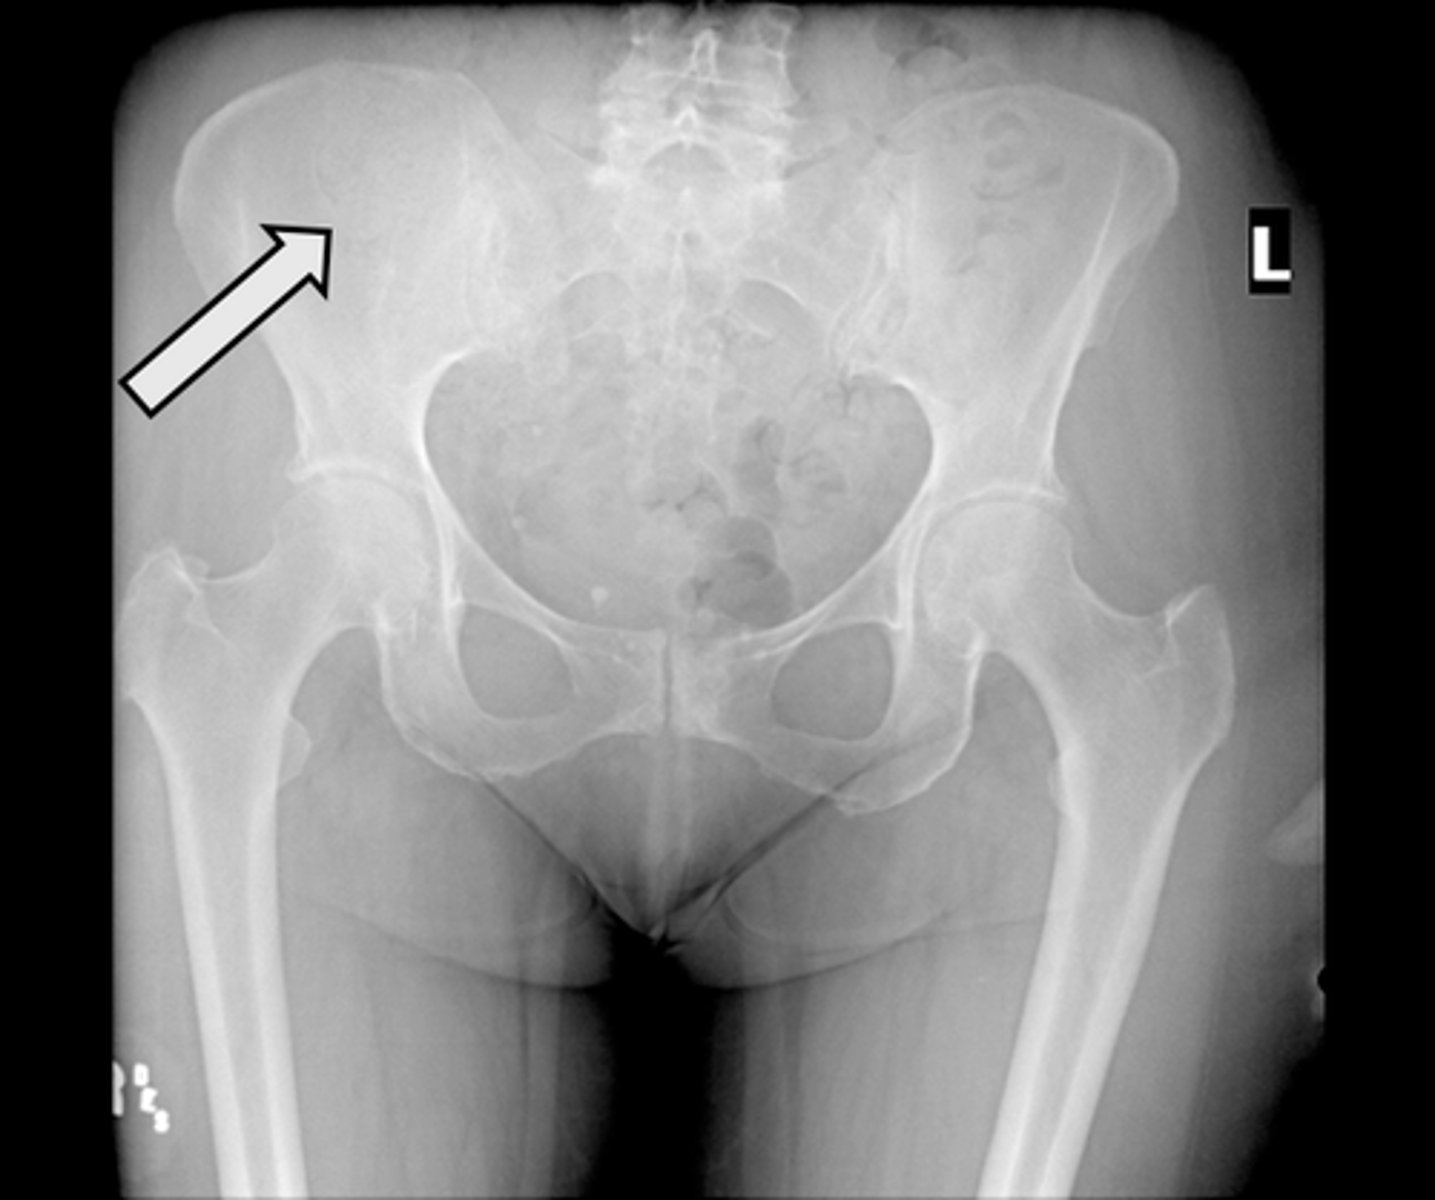

AP pelvis

What is the image?

16

L acetabulum

<p>What is indicated in the image?</p>

New cards

What is indicated in the image?

18

L ilium

20

L obturator foramen

22

L superior ramus of pubis

24

R anterior superior iliac spine (ASIS)

26

R ischial tuberosity

28

R sacroiliac joint

30

Sacrum